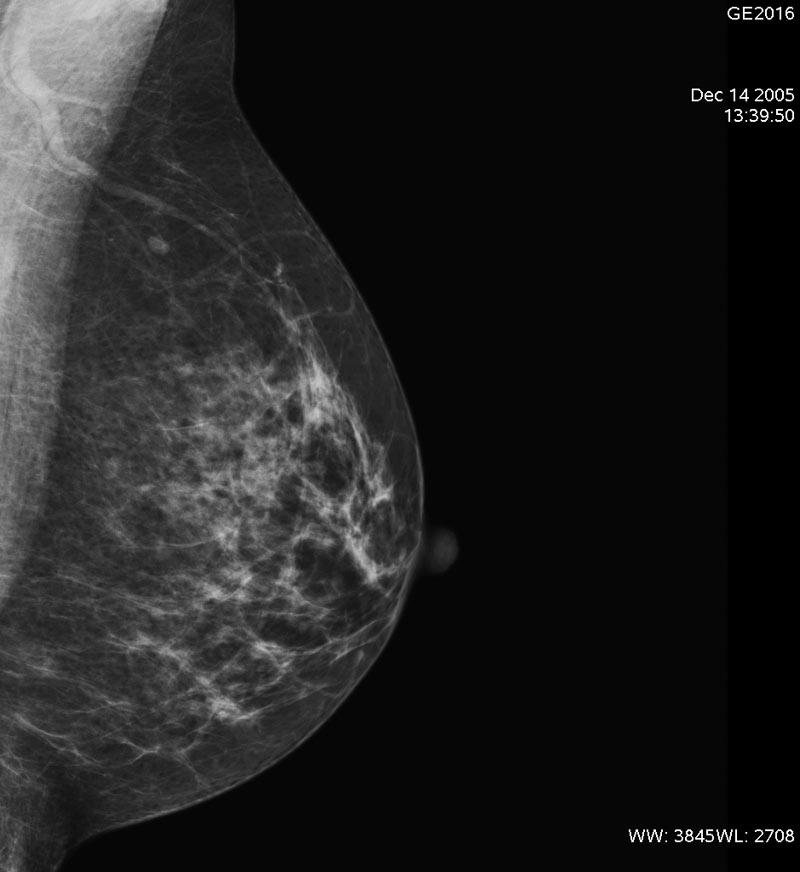

La mammografia è un esame radiografico che consente di visualizzare la ghiandola mammaria e le sue eventuali patologie, quali ad esempio la presenza di noduli non ancora palpabili.

Lo screening del seno, secondo le indicazioni del Ministero della salute italiano, si rivolge alle donne di età compresa tra i 50 e i 69 anni e prevede l'esecuzione ogni due anni della mammografia.

In questa fascia d'età si concentra infatti il maggiore rischio per il seno e, secondo gli esperti, la partecipazione allo screening può ridurre del 35% il rischio di malattie e/o patologie del seno.